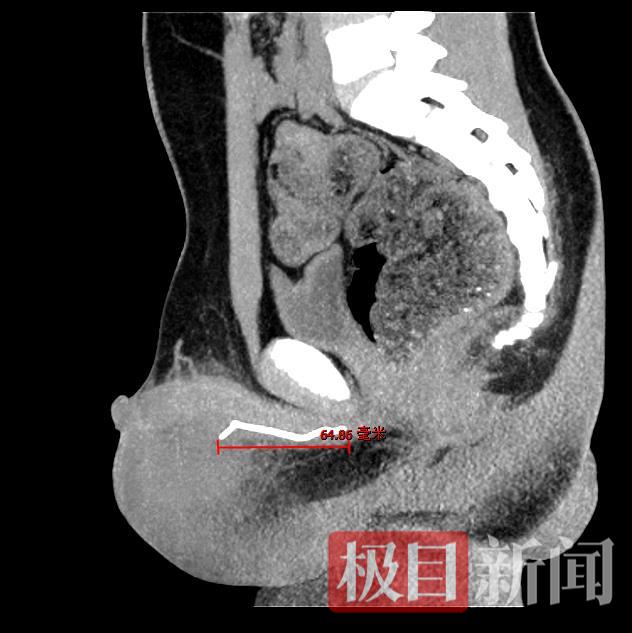

没想到,这一扫竟有意外发现:小瑞的尿道深处“潜伏”着一个条索状异物,末端已穿透尿道扎到阴囊处,被周围水肿黏膜层层包裹,因此蒙蔽了彩超“视野”。

经测量,这根“潜伏”多日的铁丝长约7厘米。